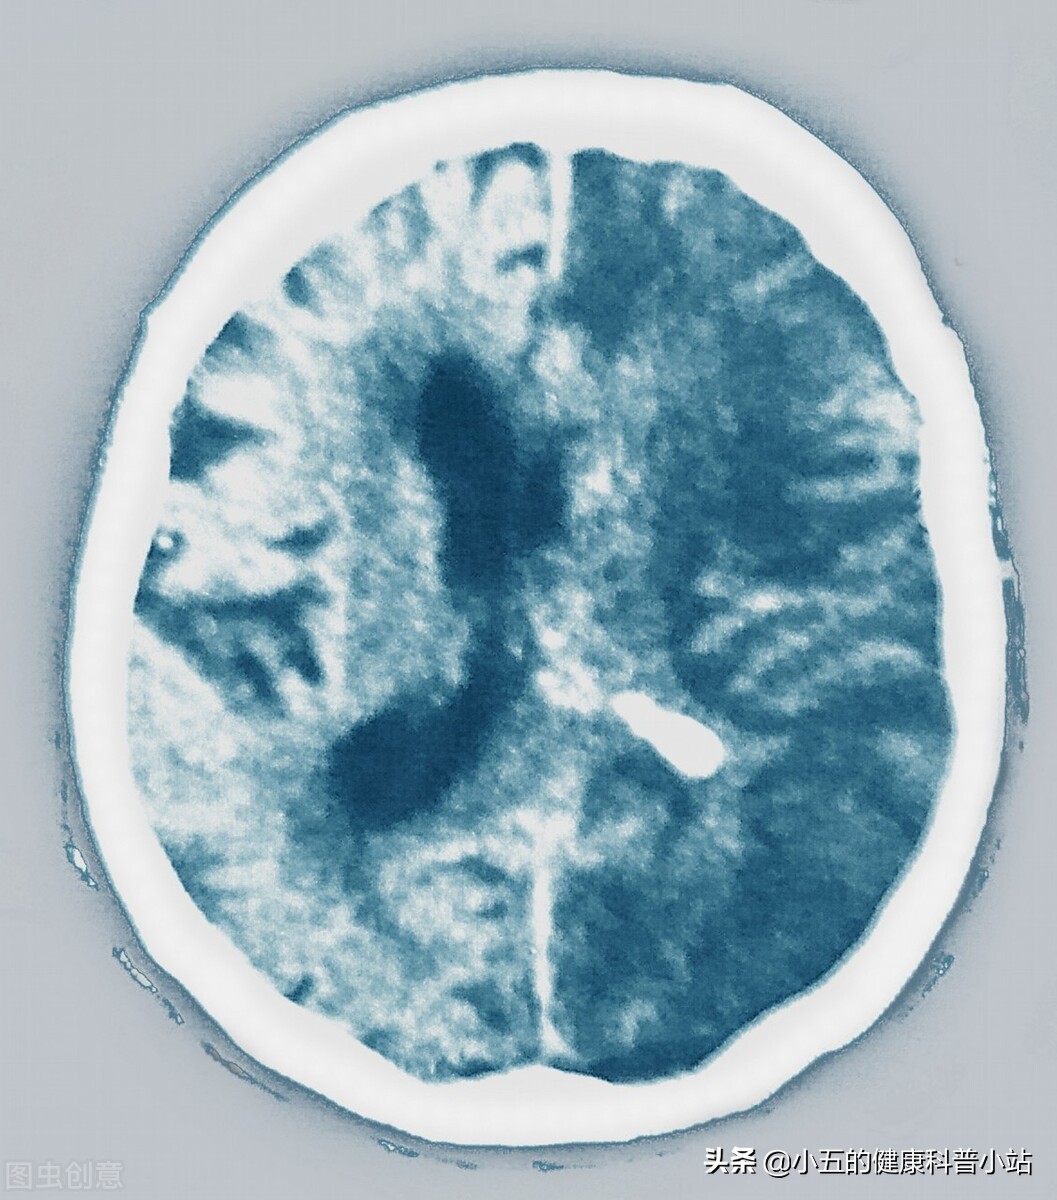

脑卒中

房颤时心房丧失收缩功能,血液容易在心房内淤滞而形成血栓,血栓脱落后可随着血液流至全身各处根据统计房颤患者出现脑卒中的几率是没有房颤患者的15-20倍 ,2003年底我国发表了中华医学会组织的中国除*藏西**以外大陆内地40家医院近万人1999~2001年房颤的回顾性研究结果表明房颤患者中脑卒中的发病率为17.5%,其中42.3%恢复功能‚49.7%中、重度致残‚8.0%死亡。其次,房颤的患者还容易诱发肢体动脉栓塞,也就是血栓进入肢体动脉中造成动脉栓塞,肢体动脉栓塞的患者会出现突发性的剧烈疼痛,伴有肢体快速肿胀,严重时甚至发生肢体缺血性坏死,要截肢才能彻底治疗。